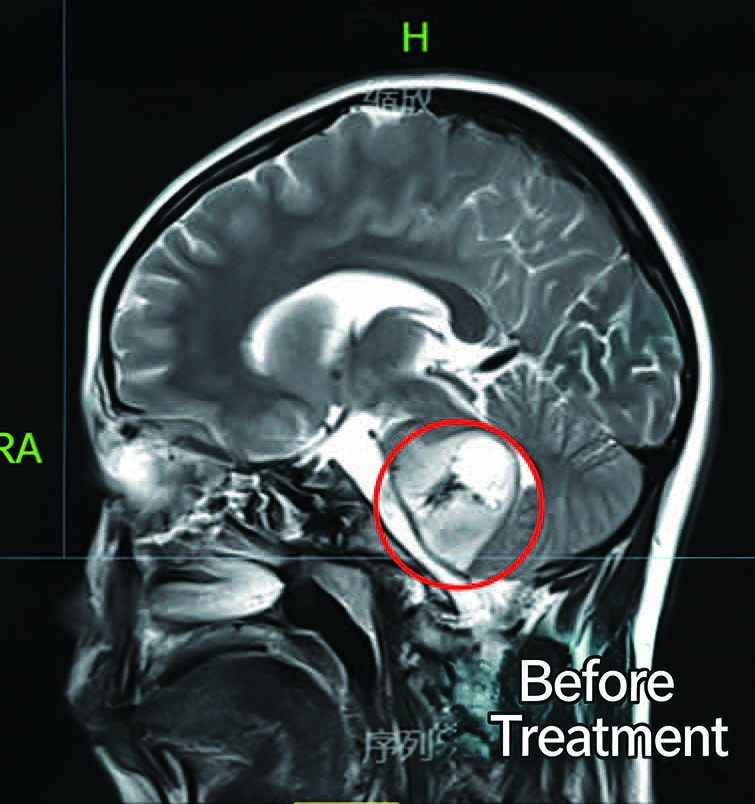

Before Treatment

After Treatment

Patient: 10-year-old female

Diagnosis: Brain Malignant Tumor (Glioma)

Symptoms: Weakness in the legs, unclear speech

Treatment:Started CyberKnife radiotherapy on June 14, 2020

Radiation dose to P丁V: 25 Gy in 5 fractions (5 Gy per fraction)

Outcome:Follow-up imaging two months later showed a slight reduction in the brainstem tumor. The patient regained consciousness, with significant improvement in speech function and gradual normalization of limb movements.